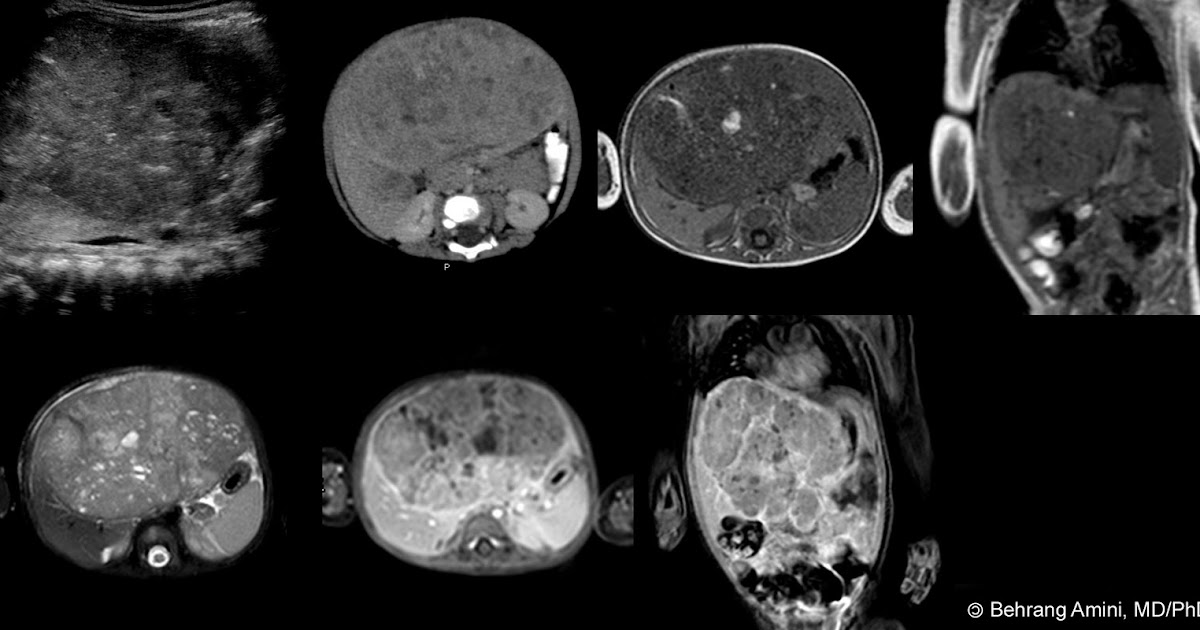

(A) Unenhanced axial fat suppressed T1weighted imaging shows the Spoke Wheel Liver Lesion Focal nodular hyperplasia (fnh) is a common, benign, nonneoplastic, mass forming lesion of the liver. The “spoke wheel” sign is a characteristic radiological finding of hepatic focal nodular hyperplasia (fnh). The management is conservative because fnhs do not undergo malignant changes. The spoke wheel sign is described in focal nodular hyperplasia (fnh) and describes the pattern of internal vasculature of. Spoke Wheel Liver Lesion.

FNH in a 22year female. (A) On gray scale sonogram a hyperechoic lesion Spoke Wheel Liver Lesion The “spoke wheel” sign is a characteristic radiological finding of hepatic focal nodular hyperplasia (fnh). It is often isoechoic to liver parenchyma on b‐mode. Focal nodular hyperplasia (fnh) is a benign lesion occurring in a background of normal liver. The spoke wheel sign is described in focal nodular hyperplasia (fnh) and describes the pattern of internal vasculature of fnhs seen. Spoke Wheel Liver Lesion.